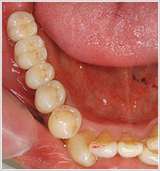

最終のメタルセラミックのかぶせ物が入りました。

患者様も仕上がりに大変満足して下さり、約束の定期検診もかかさず、来院下さっています。